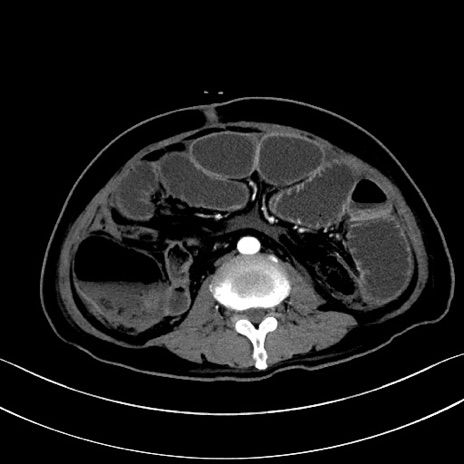

症例28(横断像)

【症例】60歳代男性

【主訴】嘔吐

【現病歴】胃癌にて胃全摘後。食思不振が悪化し、夜中に嘔吐することがある。

【既往歴】胃癌、胃全摘、脾摘、胆摘後

【データ】WBC 5900、CRP 10.56